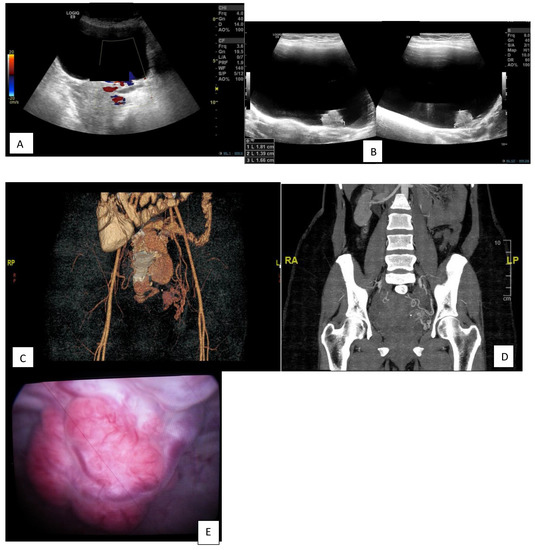

| Ultrasound | Incidental finding of large bladder mass |

| Computed tomography with contrast medium | Showed a 17.1 × 24.2 mm polypoidal hyper-vascular lesion, as previously described, arising from the urinary bladder wall (and thus unlikely to be arising from the anterior wall of the uterus). |

| Cystoscopy | Showed a large, bluish-red, pulsatile, vascularized submucosal mass with large dilated submucosal vessels, a wide-based stalk and no active bleeding in the posterior wall of the urinary bladder, measuring about 2 × 3 cm, with urine cytology negative. |

| First angioembolization | Selective catheterization of the left internal iliac artery using a C2 angiocatheter followed by angioembolization of the left superior vesical arteries, approaching from the anterior division of the left internal iliac artery. |

| In 2018, recurrence after 5 years of follow-up | US showed a distended UB with a polypoidal soft tissue mass measuring 16 × 16 mm with internal vascularity, nidus in afferent and efferent vessels, and turbulence in the flow. |